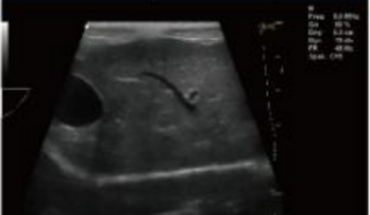

- Equipped with a Wide Range of Probes for Abdominal, Obstetric, Vascular, Cardiac, Small Organ, Urinary Applications

Rich Clinical Application Function